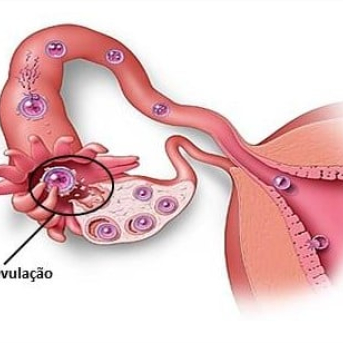

Os médicos aconselham a utilização dos remédios para engravidar em mulheres que tem ovulação irregular ou que tem ausência total da ovulação. Obviamente após investigação do casal, no caso da mulher com ultrassonografias para verificação de obstrução de trompas e o homem espermograma para verificação da qualidade do sêmen.

O foco dos remédios são melhorar a qualidade e quantidade dos óvulos, sendo um processo cuidadoso e ponderado pelo especialista, pois ao obter muitos óvulos é arriscada a gestação de múltiplos, gêmeos, trigêmeos etc. A indicação dos remédios para engravidar também ocorre para casais que são tentantes há um período superior a um ano e não conseguiram a gestação de forma natural.